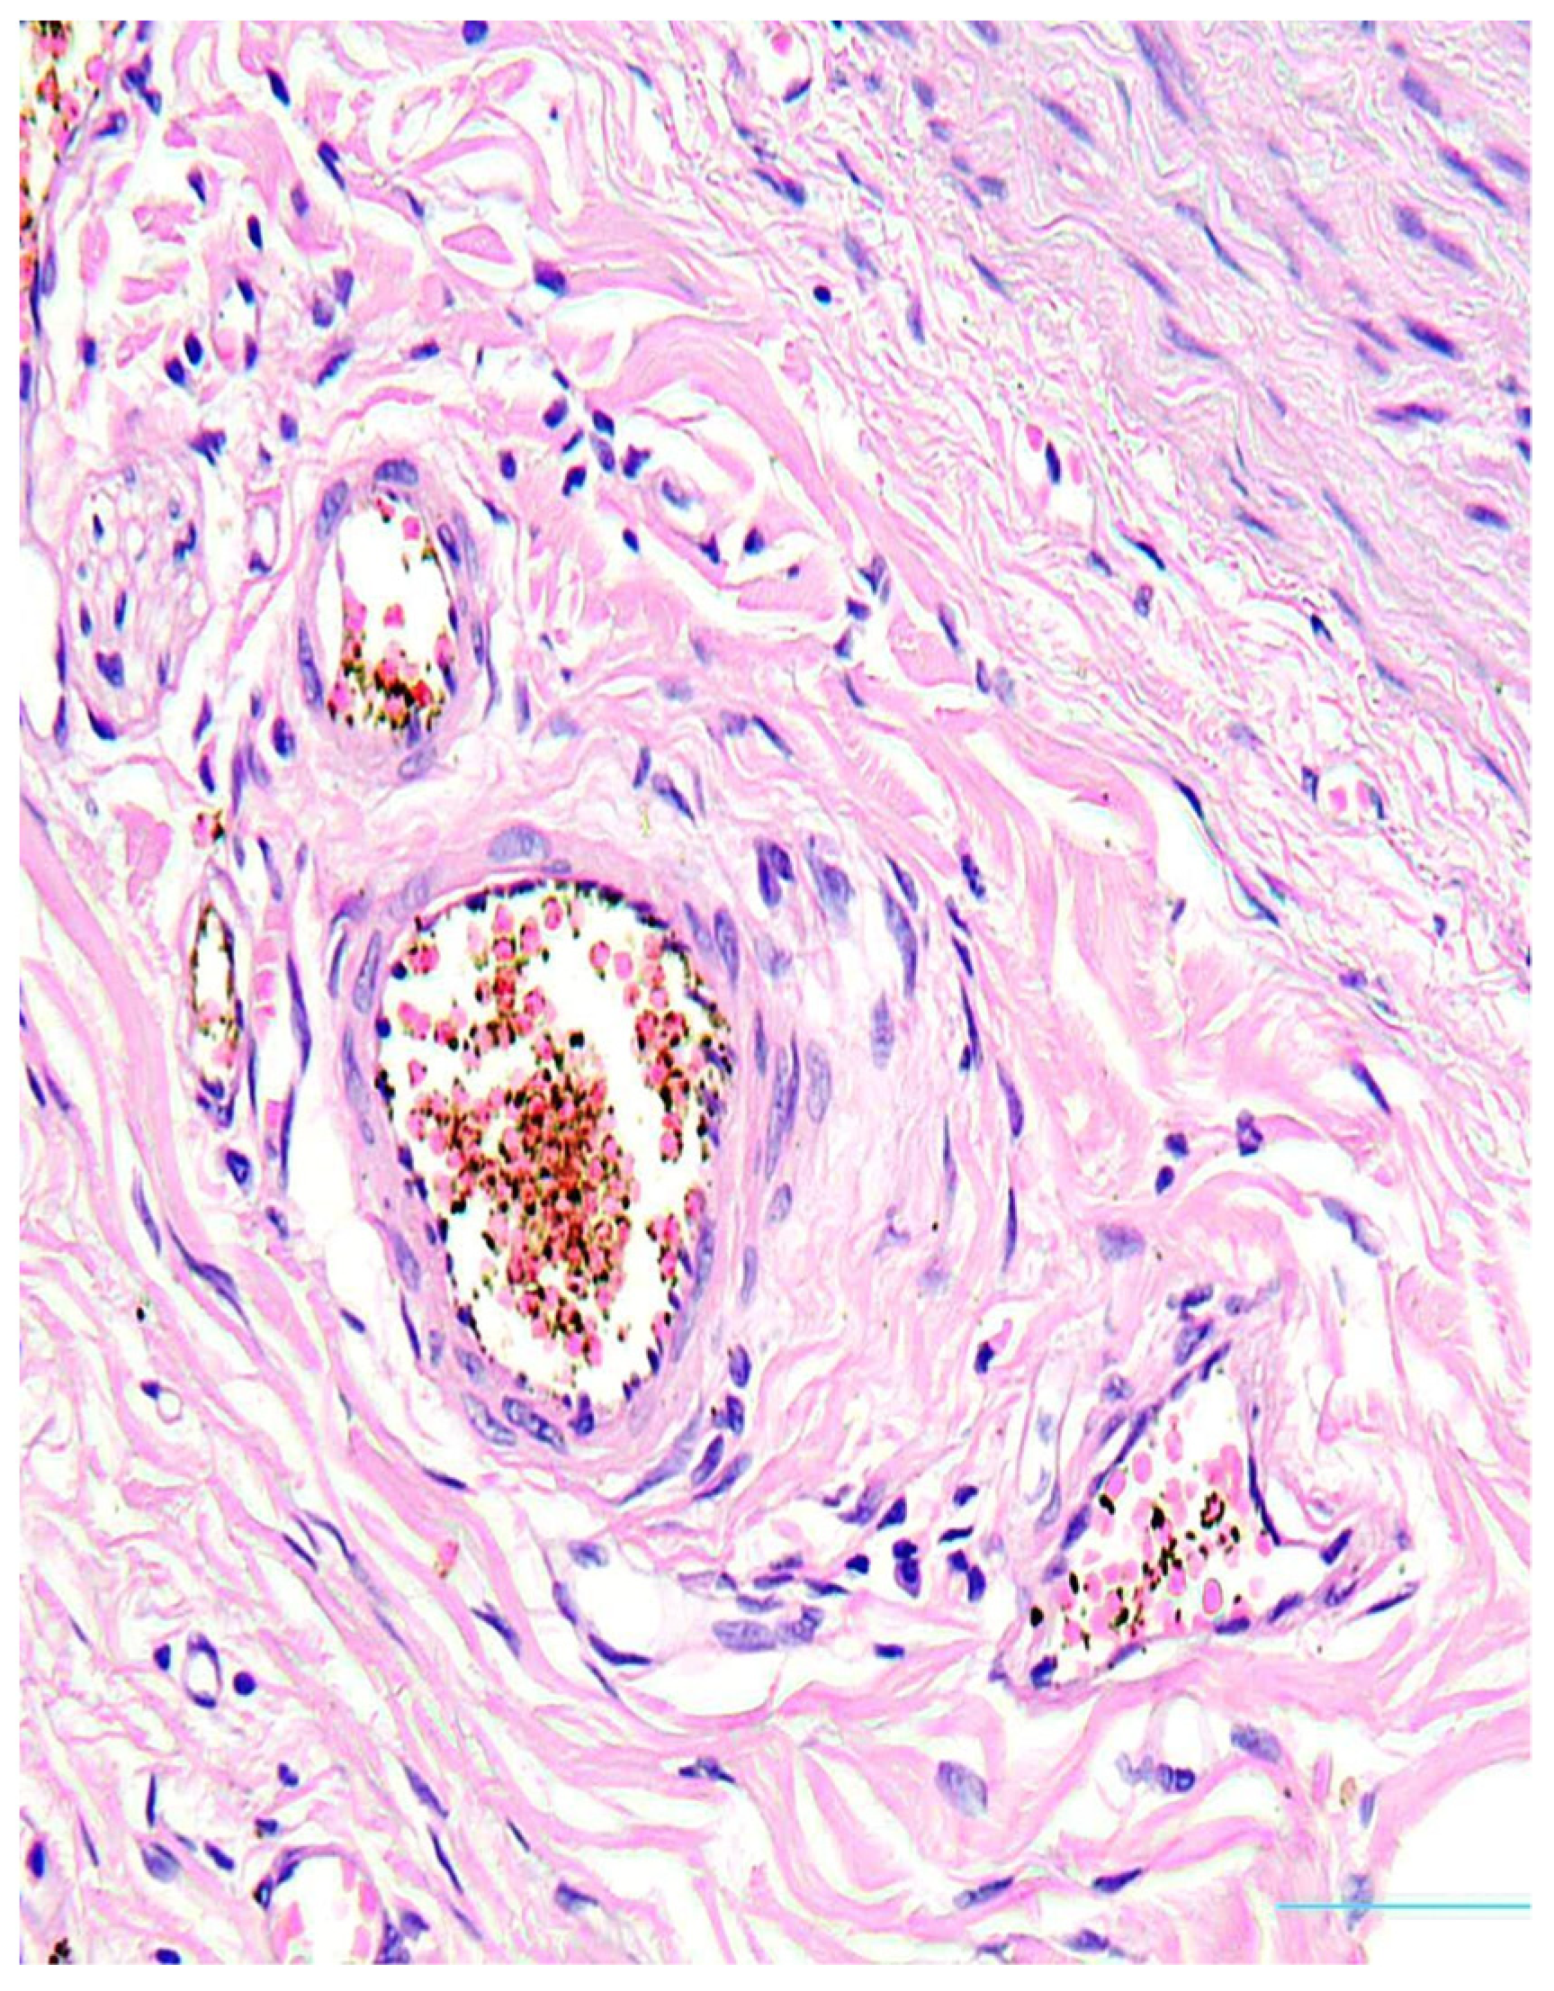

2. Case Presentation